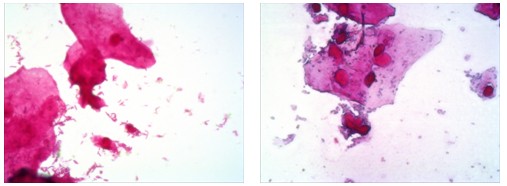

安圖公司目前主要是為終端用戶搭配一套用于分析記錄革蘭氏染色的數(shù)碼生物顯微鏡,廣州明美為鄭州安圖生物公司提供了高性價比的500萬像素顯微鏡相機MD50,并由武漢辦事處的工程師就近提供安裝培訓(xùn)服務(wù)。以下是廣州明美500萬像素顯微鏡相機MD50搭配奧林巴斯生物顯微鏡CX31所獲取的革蘭氏染色片子的高品質(zhì)顯微圖像:

革蘭氏染色分析

通過熒光顯微鏡|顯微鏡攝像頭|顯微鏡接口獲取的優(yōu)質(zhì)的革蘭氏染色的顯微圖像效果,用戶可以通過電腦屏幕輕松的進行細菌的分析判斷,將雙眼從高強度的鏡檢中解放出來,大大降低勞動強度,同時可以方便的進行信息的儲存以及共享。